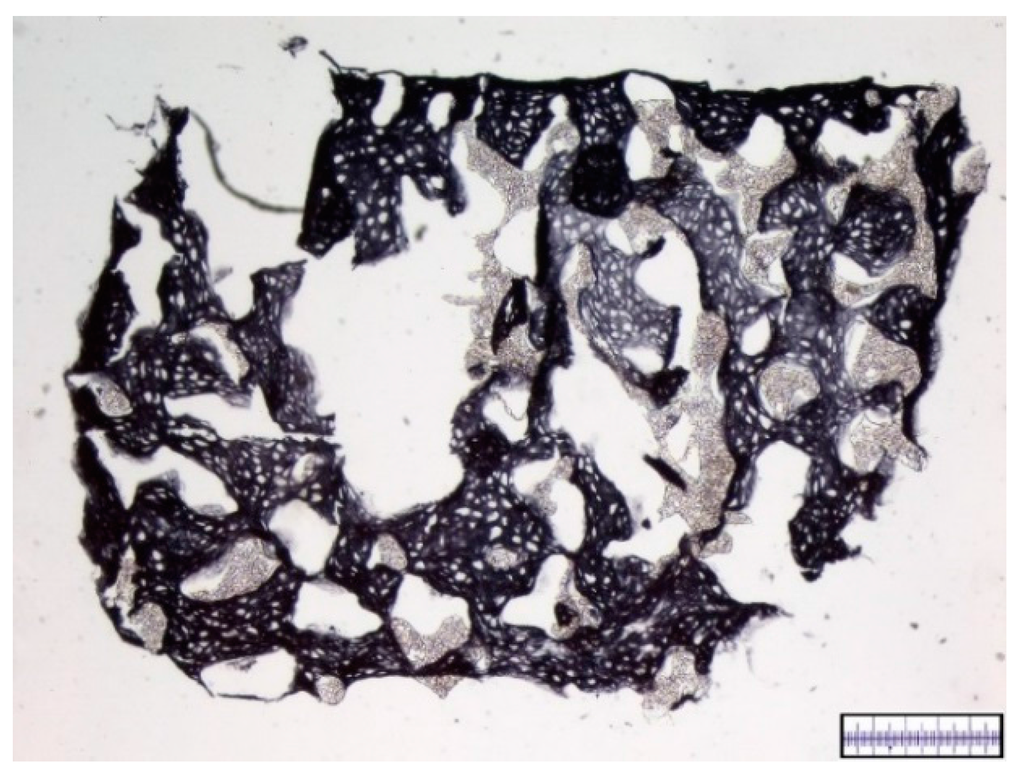

3.2. Interconnectivity of Scaffold Pores